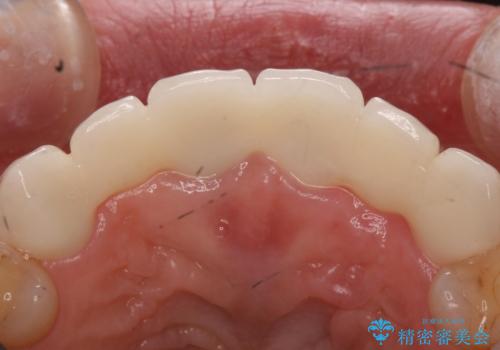

根の状態も良くなかったため、根管治療から行うこととなりました。

左上2番の歯は歯根が割れていたため抜歯し、入れ歯をブリッジに変えていきます。

- 右上1左上1:根管治療(リトリートメント)+土台(ファイバーコア)/99,000円×2本+22,000円×2本 右上123左上123:仮歯+ジルコニアクラウン(スタンダード):11,000円×6+121,000円×6 計1,034,000円(税込)費用は治療当時の料金となります